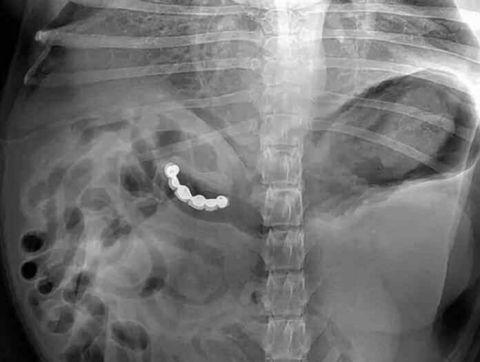

这是个吞别针自杀的